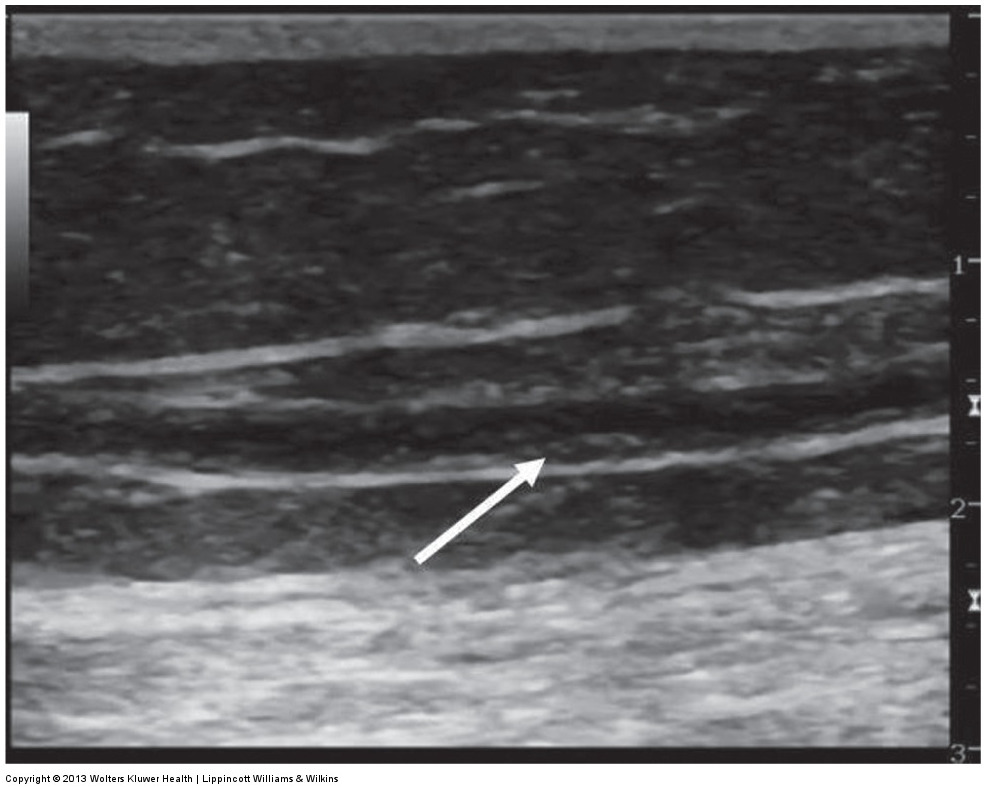

ultrasound image of a thickened recanalized vein